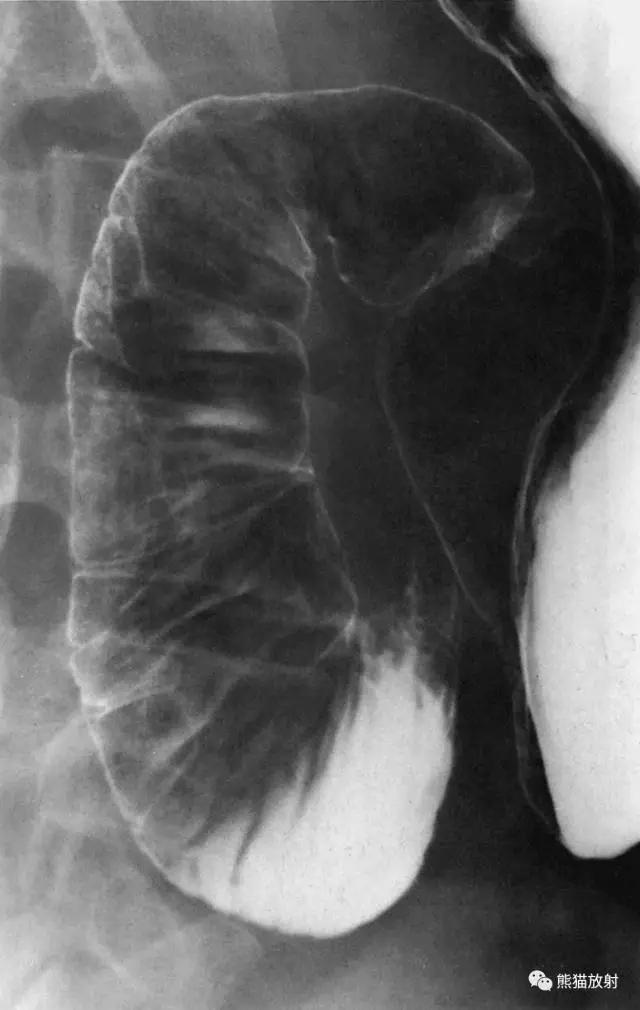

5 Stomach 胃

1 Fundus 底,2 Abdominal esophagus 腹段食管,3 Cardia 贲门,4 Lesser curvature 小弯,5 Duodenum 十二指肠,6 duodenal bulb 十二指肠球部,7 Gastric folds (posterior wall) 胃皱襞(后壁),8 Pylorus 幽门,9 Body of the stomach 胃体,10 Angular notch 角切迹,11 Greater curvature 大弯,12 Pyloric antrum 幽门管,12 + 13 Antrum 胃窦